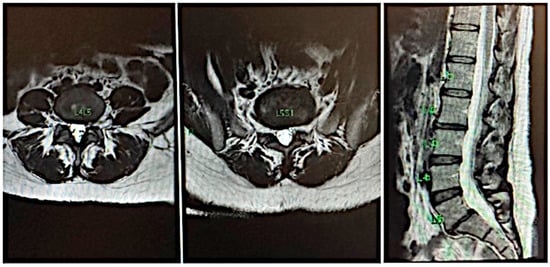

4. CASE 3: Lumbar Disc with Compression and Central Stenosis